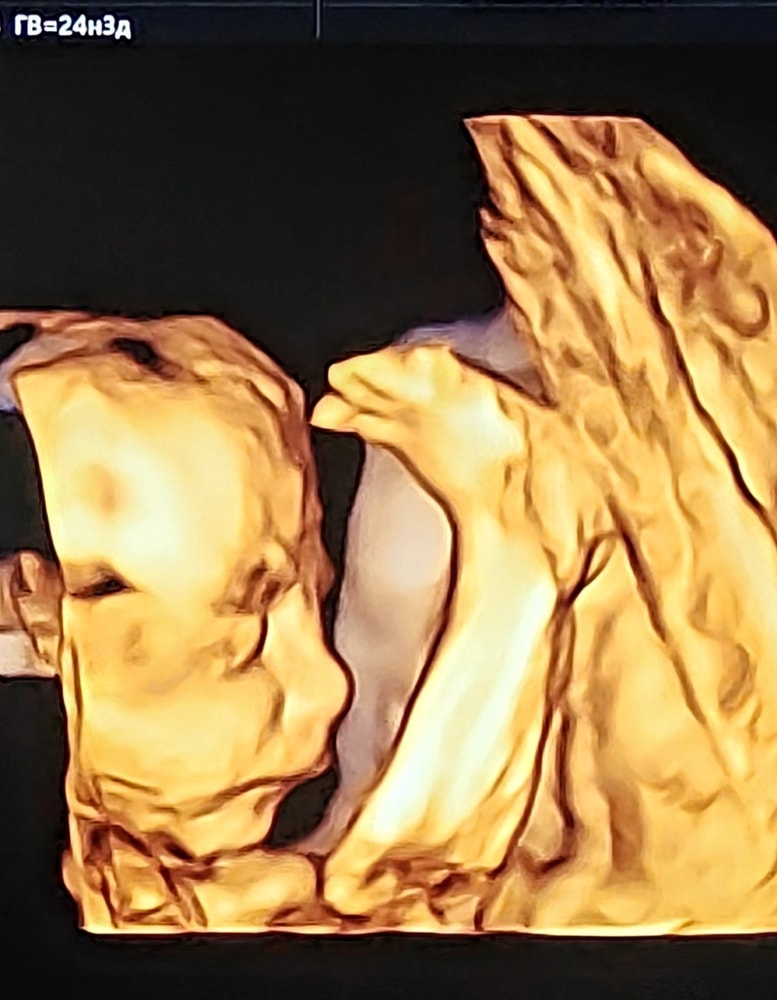

24+3

УЗИ, КТГ, доплерПошли фотографироваться для бабушек и дедушек.

Рост ног у человека опережает все остальное на 2 недели, но он приспособился 😁 Обнаружили его сложенным пополам.

Примерно с 11 недели стало ясно, что позы малыша повторяют позы мужа. УЗИ выпадало обычно на выходные, и мы шутили, что сын лежит в типичной позе "субботнее утро айтишника", только мака на коленках не хватает.